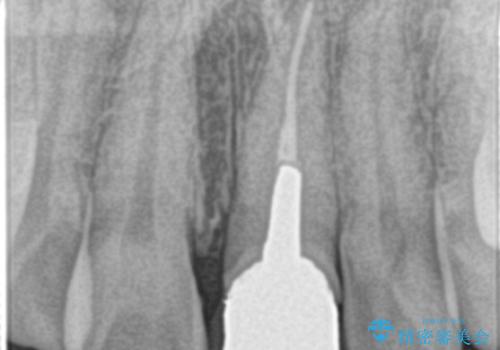

- 前歯の変色を主訴に来院されました。

根管治療は希望されなかったので、リスクを説明した上でオールセラミッククラウンの治療を行っています。

金属の被せ物は歯肉の変色を起こしやすくなります。オールセラミッククラウンは金属を使わないため審美的な治療を行うことができます。